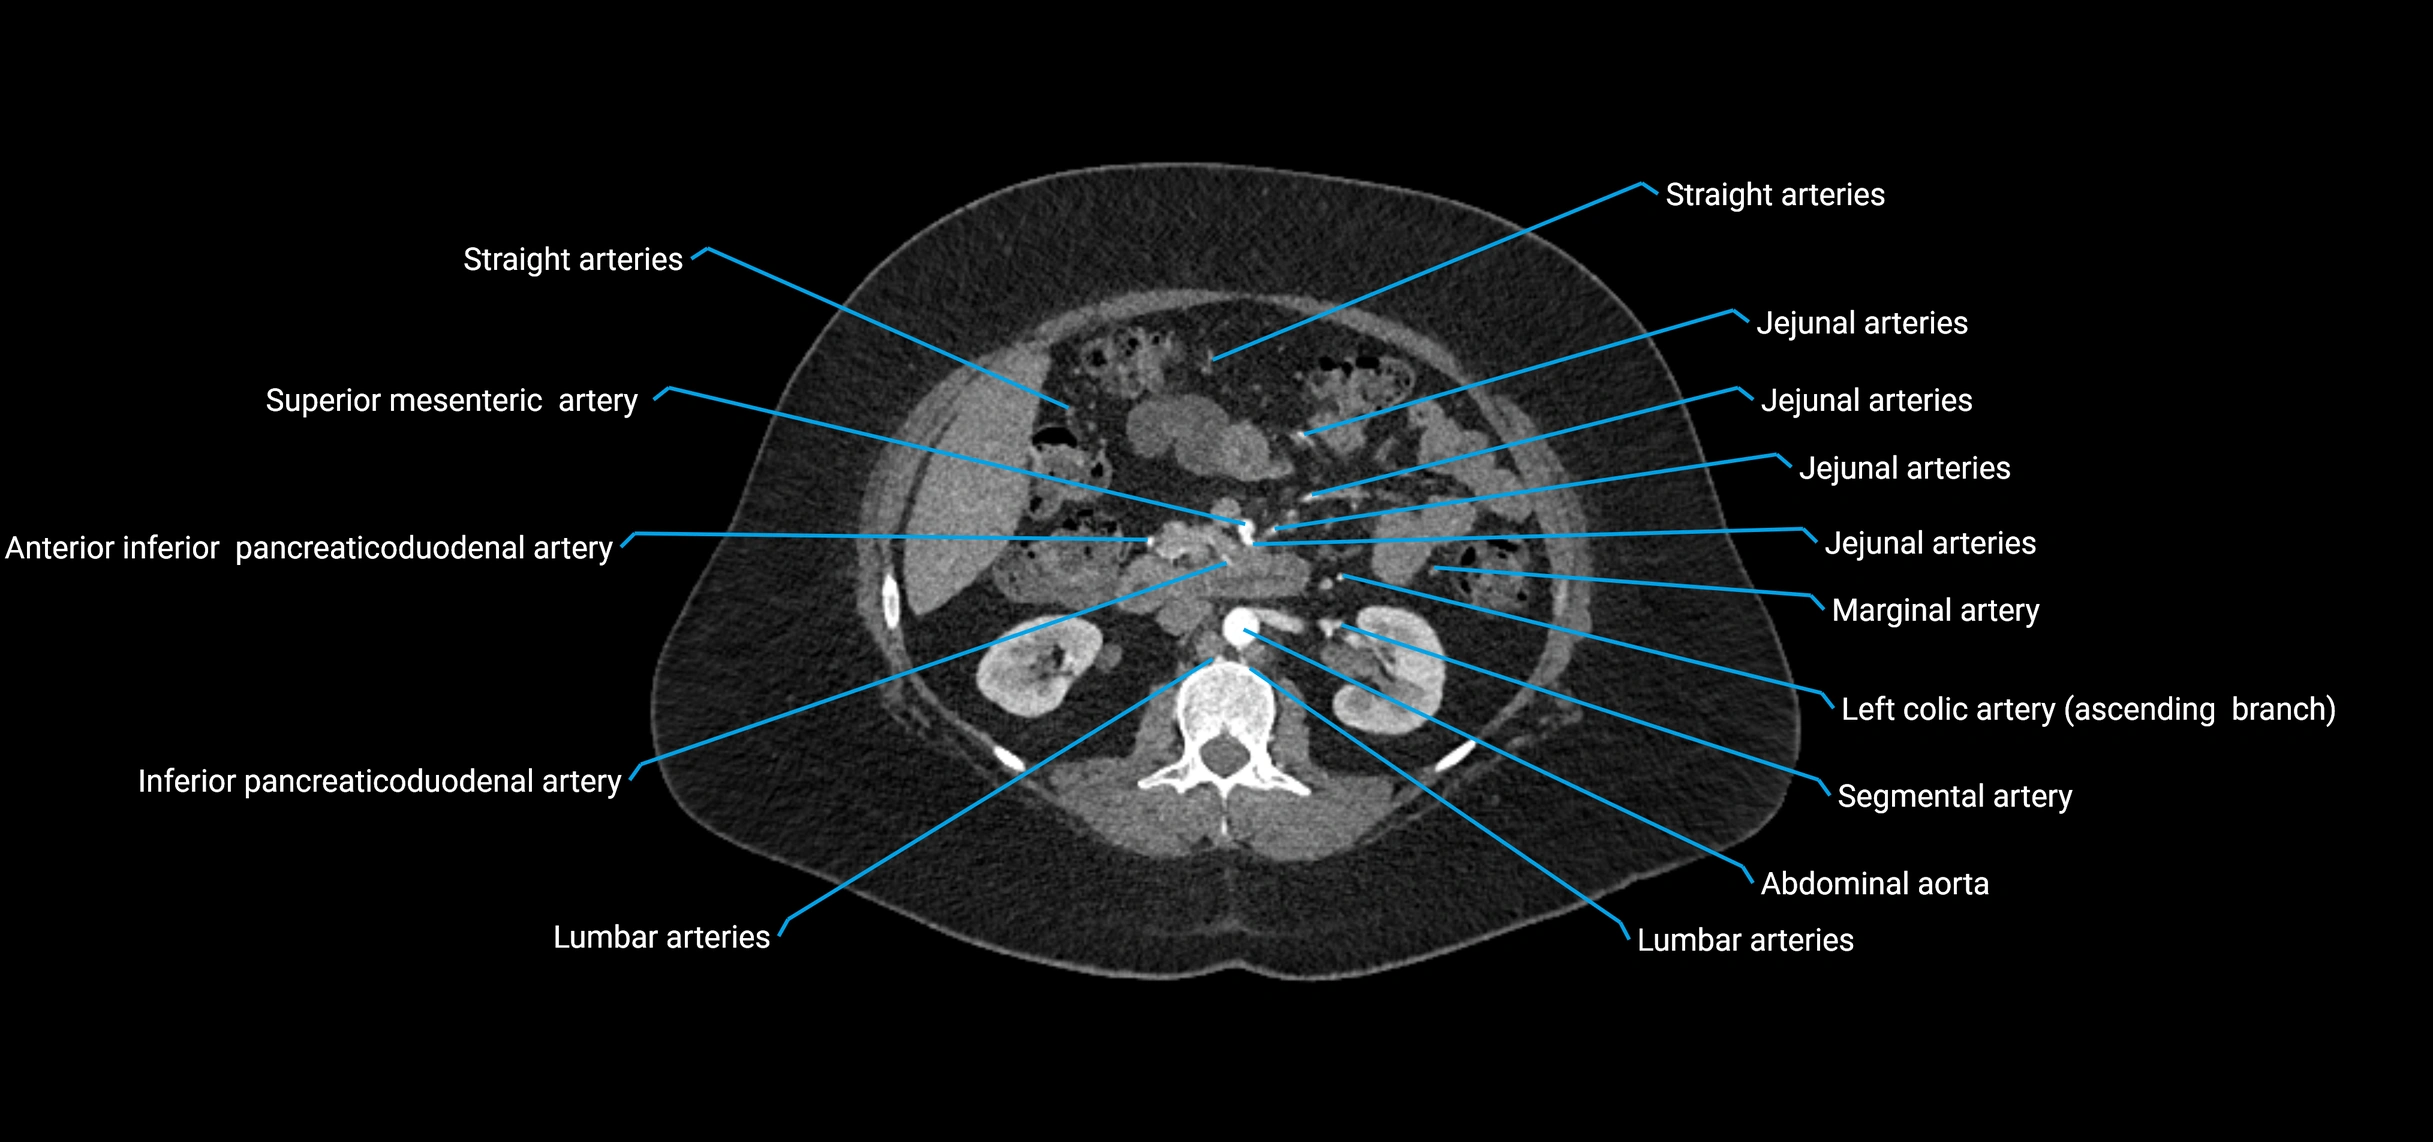

Contrast-enhanced CT (CTA):

• Gold standard for abdominal aortic imaging

• Provides excellent detail of lumen, wall, aneurysm, thrombus, and branch vessels

• Multiplanar and 3D reconstructions help in aneurysm measurement, stent graft planning, and dissection evaluation

• Detects acute rupture, traumatic injury, or occlusion with high sensitivity